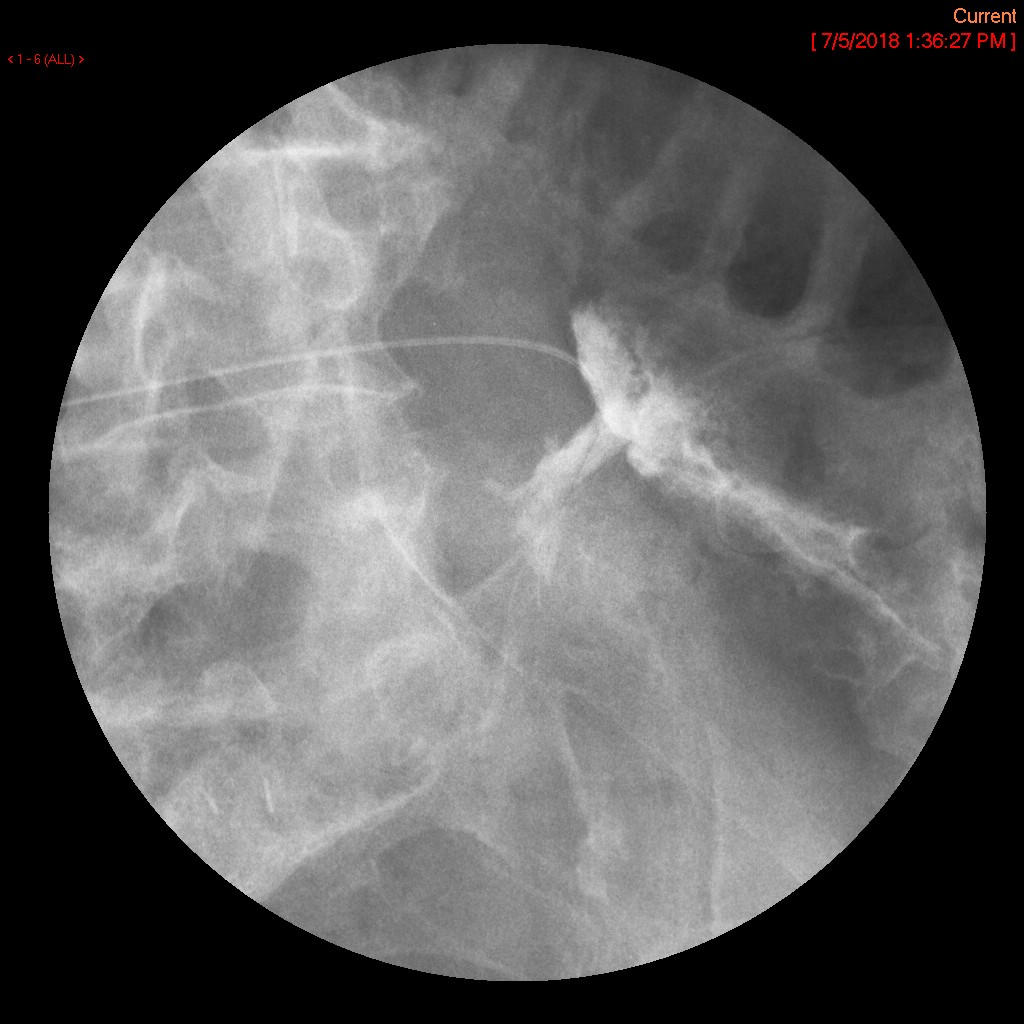

- Once you have the tube in the desired location, inject water soluble contrast material through the tube to verify location. Immediately after injection, obtain a spot image or do a screen capture showing final tube position.

- nasoduodenal

(key image 1)

- nasojejunal

(key image 2)